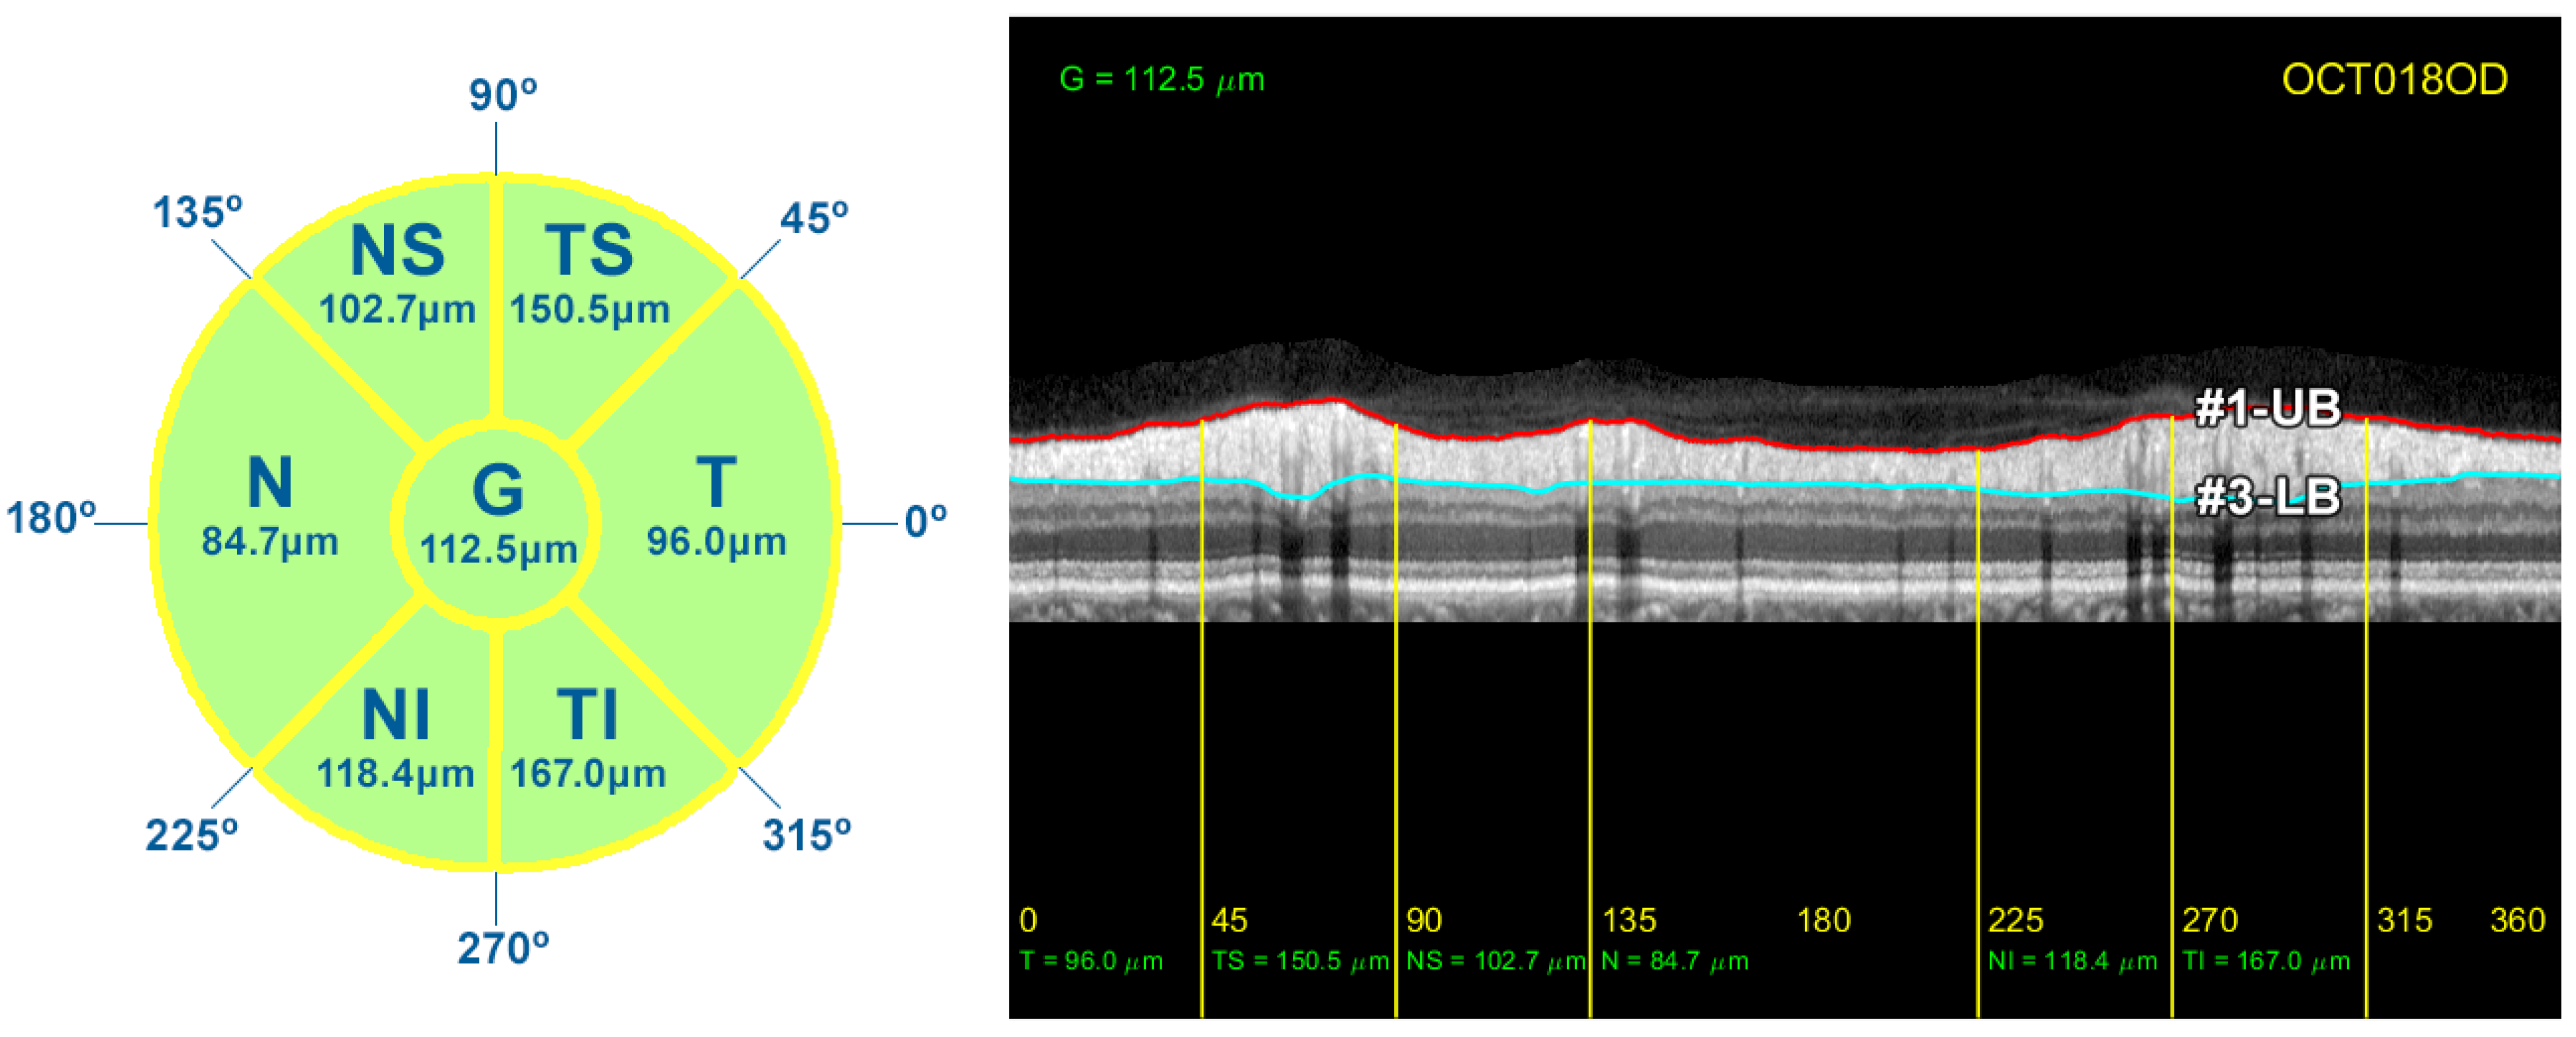

As described in Section 1, the thickness of the RNFL and GCL is important for monitoring the progression of ocular diseases such as glaucoma. In order to compare the results provided by the proposed method with the measurements given by the OCT device, the circumpapillary RNFL thickness was averaged by sectors (T, TS, NS, N, NI, and TI), and the global mean value was also calculated (G). The thickness of the RNFL was calculated by simply subtracting the position of contours #1-UB and #3-LB, resulting in a vector w with the thickness of the layer at each x-coordinate of the image I. The correspondence between the x-coordinate and the polar coordinate of the analysis circumference is detailed in Table 2 and depicted in Figure 3. This vector w allowed us to calculate the average value of the RNFL thickness in all the different sectors of the eye. Figure 14 displays the resulting measurements for the OCT image used in the description of the method.

Figure 14.

RNFL thickness measurements for each sector of the peripapillary circumference. On the left, diagram detailing the value of the average thickness of the RNFL in each sector of the eye. On the right side, representation of the borders #1-UB and #3-LB, and the average RNFL thickness in these sectors.